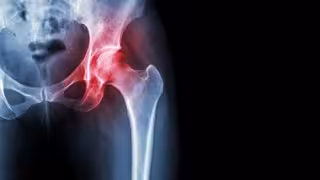

Archivo - Necrosis avascular de cadera.

Archivo - Necrosis avascular de cadera. - HOSPITAL LA LUZ - Archivo